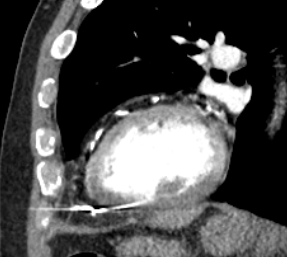

Another month later the patient presented to A&E with chest pains and a sensation that the pacemaker was delivering shocks. The CT report from the previous week was chased and revealed the following.

“Dual-chamber cardiac pacemaker is noted in situ. The tip of the right ventricular lead is seen located beyond the confines of the myocardium and abutting the pericardium. Features suggest RV lead perforation of the myocardium, on the background of clinical history provided. Urgent specialist Cardiac review is recommended.

The lead is seen traversing through the pericardial space. However, the pericardium appears grossly intact. No evidence of pericardial effusion”

Figure 3 – CT scan image showing the RV lead tip beyond the myocardial border